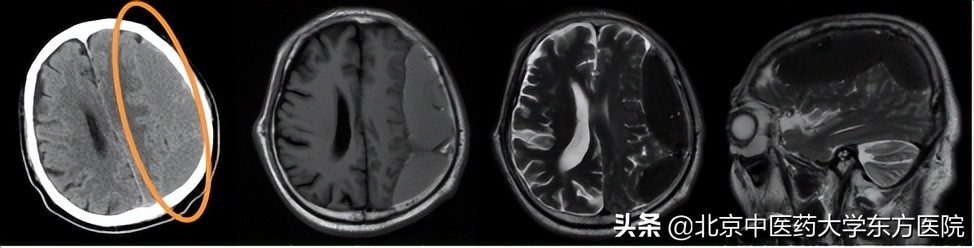

4、诊断慢性硬膜下血肿需要做哪些检查?

头颅CT或MR检查,可明确诊断。